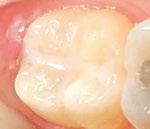

Figure 1: Preoperative periapical radiograph of tooth No. 30 with a large radiolucent lesion approximating the distal pulpal horn and a smaller radiolucent lesion closer to the mesial marginal ridge Figure 3: Conservative removal of all carious dentin on all axial walls and pulpal floor. No clinical pulpal exposure noted, but likely very close to distal buccal pulp horn Figure 2: Large active carious lesion involving the entire distal buccal cusp and surrounding aspect of tooth No. 30. Smaller Class VI lesion located on the mesial lingual cusp on No. 30 Figure 4: Placement and curing of two separate thin layers of NeoLINER over the dentin. Image depicts the NeoLINER following the indirect pulp cap of tooth No. 30